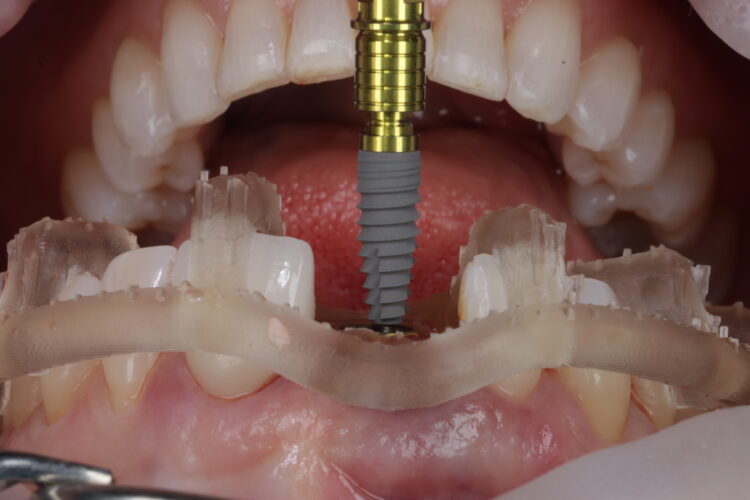

The surgical guide was checked in the mouth, ensuring it was fully seating and not in contact with the adjacent teeth.

The standard CONELOG® (BioHorizons Camlog) guided drill sequence was followed. The Guided Surgical Kit is very simple to use with a streamlined number of drills. The CONELOG® drills support primary stability, with side-cutting features and apical threads that engage the native bone.

The CONELOG® Progressive-line implant maximised primary stability and in this case the implant was inserted at 70Ncm. The pre-made temporary was used as the temporary restoration; however, there would also be the option of modifying the existing crown.

The implant was placed in close contact with the palatal bone, 1mm below the buccal bone height. A temporary cylinder abutment was connected, with flowable composite placed to attach the temporary restoration. The composite resin was used to create the optimal emergence profile ensuring a highly polished restoration in the transition zone.